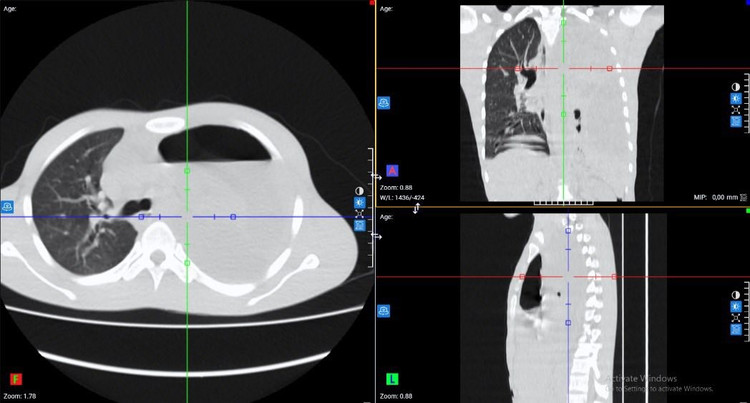

Kết quả xét nghiệm máu cho thấy tình trạng nhiễm trùng nặng với chỉ số bạch cầu (WBC) lên tới 64.8 G/L, chỉ số CRP cao 263.6 mg/dL. Với hệ thống chẩn đoán hình ảnh hiện đại, các bác sĩ ghi nhận: Đông đặc nhu mô thùy dưới phổi trái, tràn dịch màng phổi trái lượng nhiều, tràn khí màng phổi trái, phổi trái bị xẹp thụ động, đẩy lệch trung thất sang phải.

Tổn thương phổi trên phim chụp - Ảnh BVCC